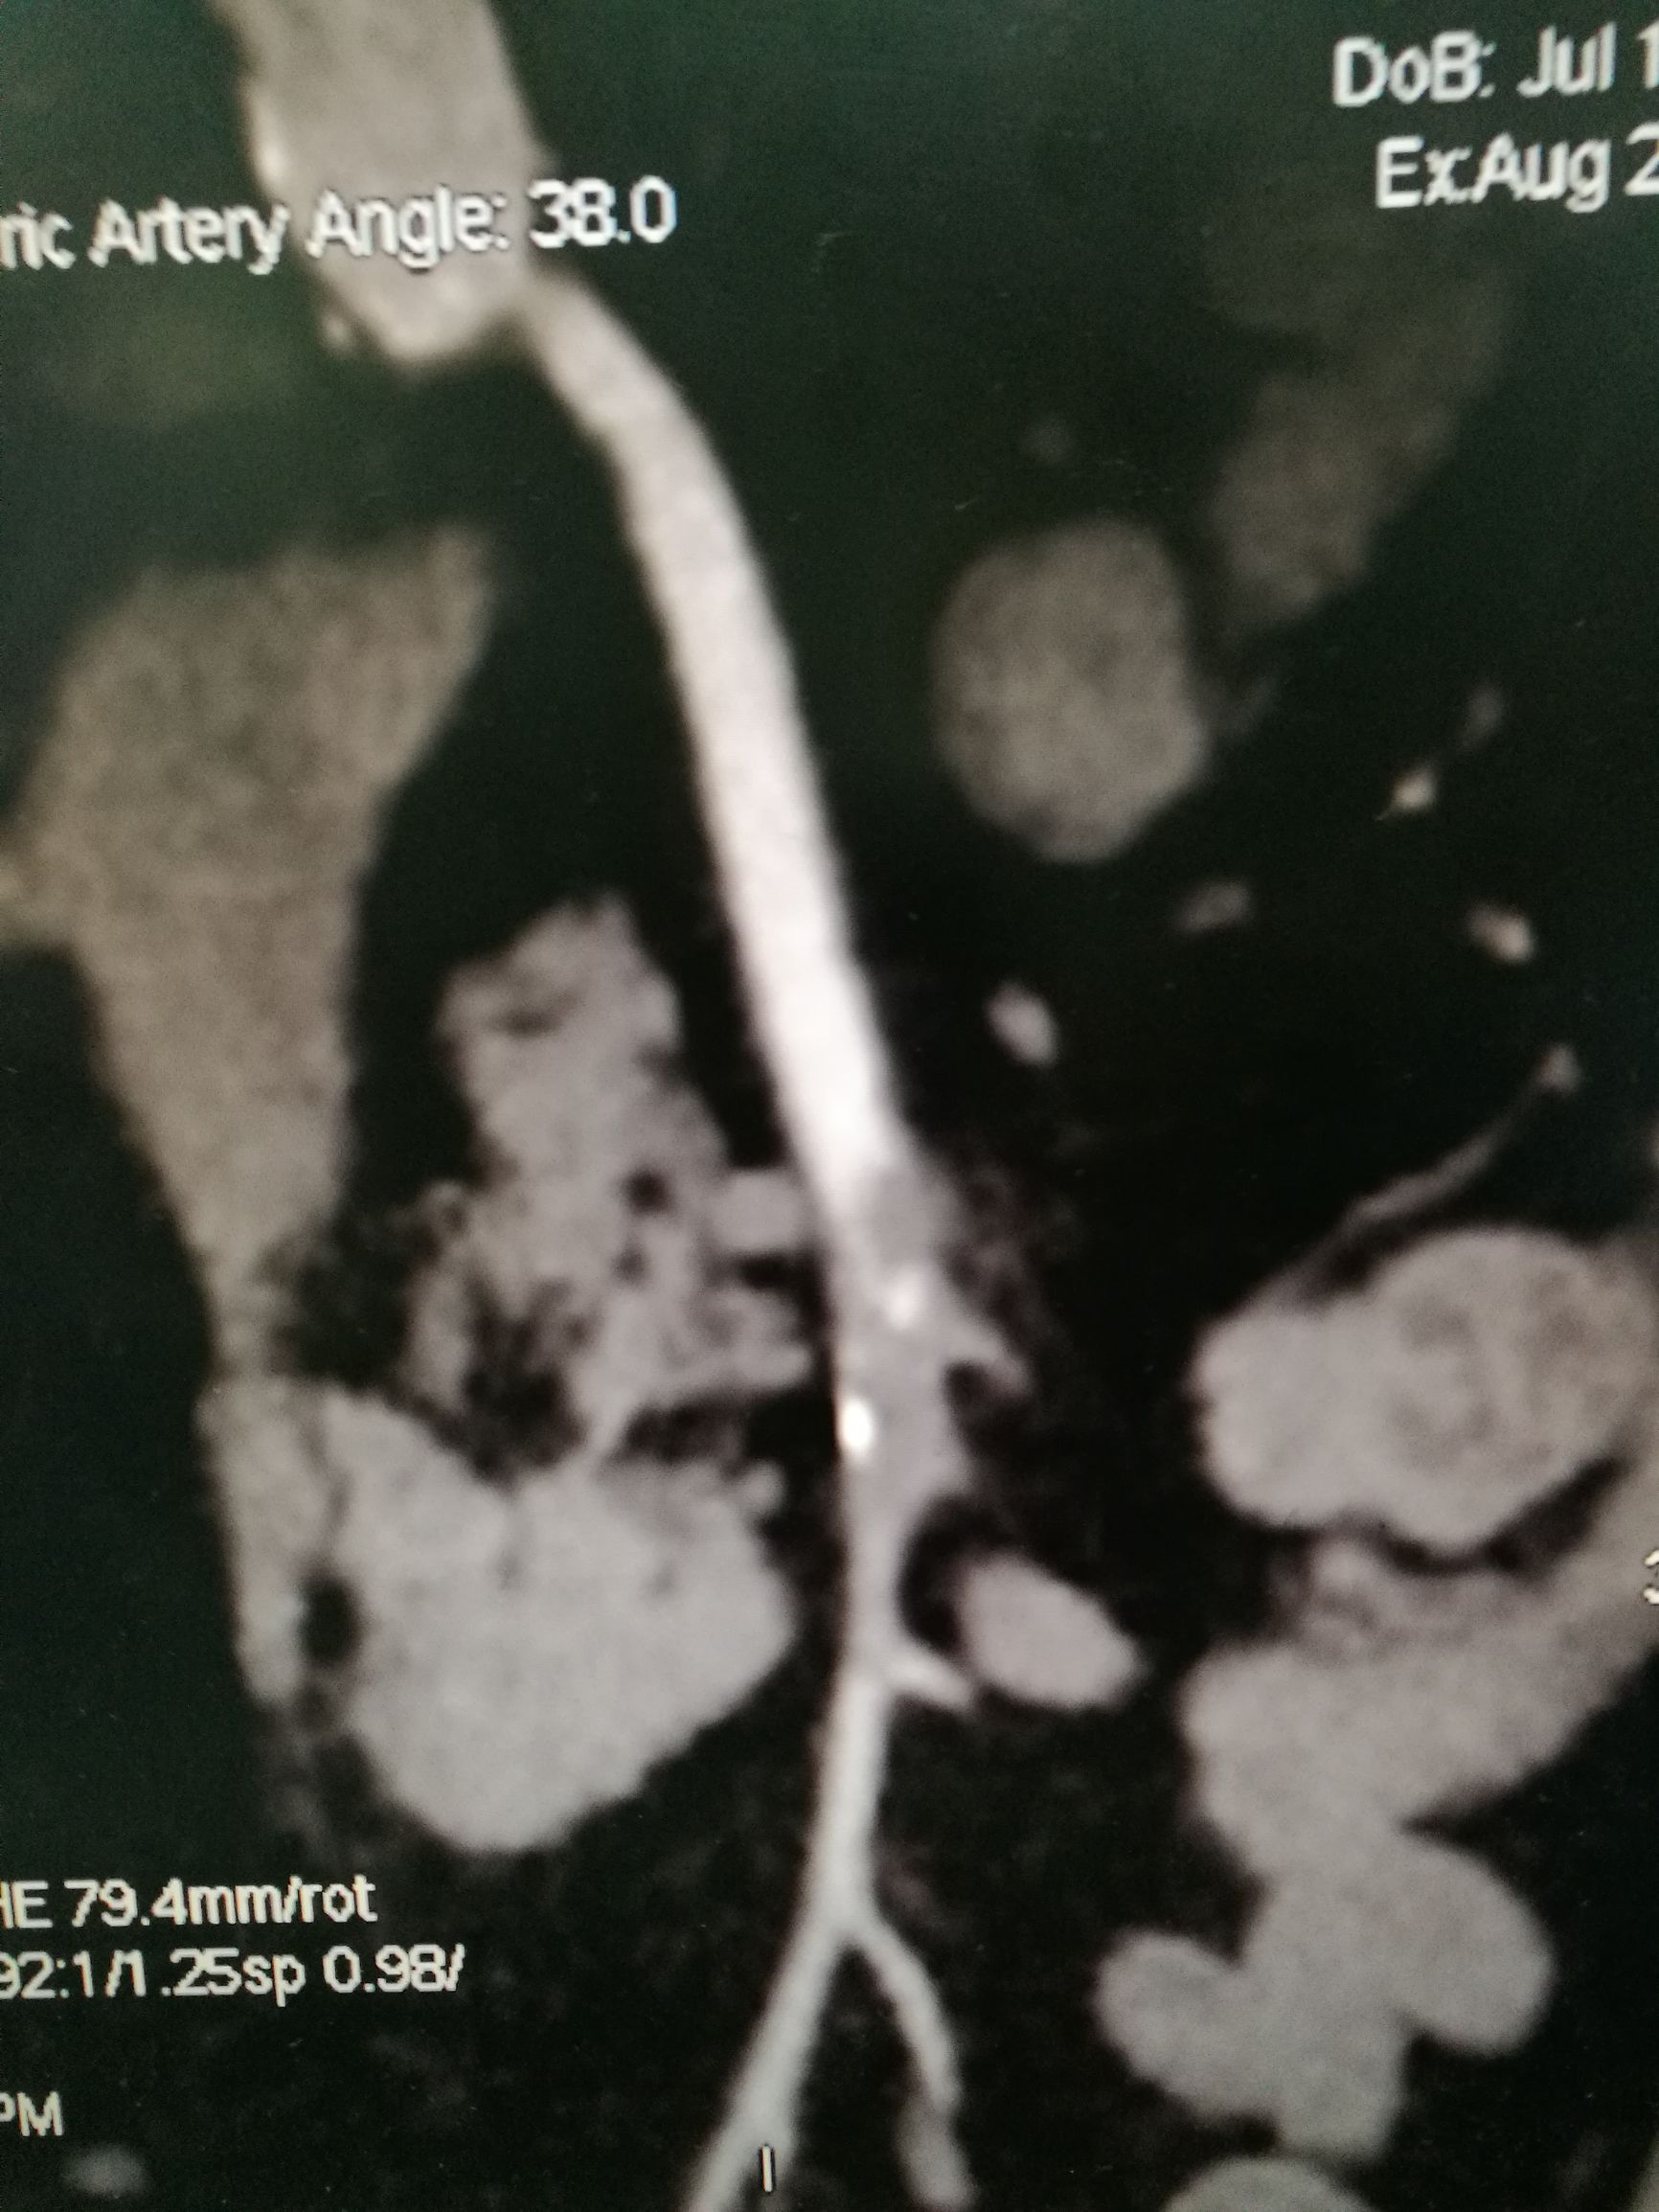

图1. 二维重建片可见肠系膜上动脉内充盈缺损

图2. 三维重建可见肠系膜上动脉中断